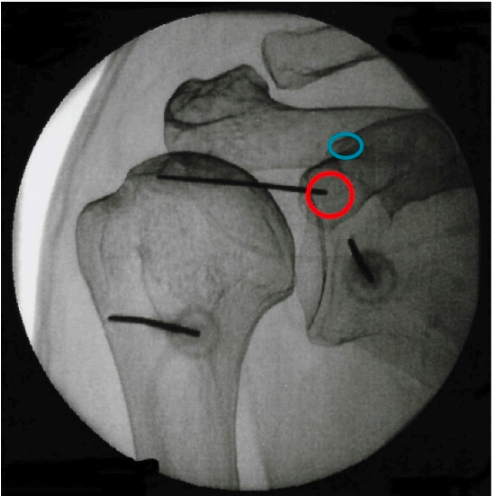

The procedure is done in operation theatre under local anesthesia. The patient is made to lie on the operation table and the appropriate joint/ spine is identified under imaging guidance. RF needle is inserted under imaging guidance to target the concerned nerve and thereafter RFA is performed using RF machine

Shoulder joint

- RFA suprascapular nerve

- RFA shoulder joint